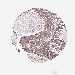

OVARIAN CANCER - Protein expressioni

A mouse-over function shows sample information and annotation data. Click on an image to view it in a full screen mode. Samples can be filtered based on level of antibody staining by selecting one or several of the following categories: high, medium, low and not detected. The assay and annotation is described here.

Note that samples used for immunohistochemistry by the Human Protein Atlas do not correspond to samples in the TCGA dataset.

Antibody stainingi

Antibody staining in the annotated cell types in the current human tissue is reported as not detected, low, medium, or high, based on conventional immunohistochemistry profiling in selected tissues. This score is based on the combination of the staining intensity and fraction of stained cells.

Each image is clickable and will lead to virtual microscopy that enables deeper exploration of all samples and also displays staining intensity scores, fraction scores and subcellular localization as well as patient and tissue information for each sample.

Antibody HPA056752

Cystadenocarcinoma, serous, NOS

Cystadenocarcinoma, mucinous, NOS

Carcinoma, endometroid